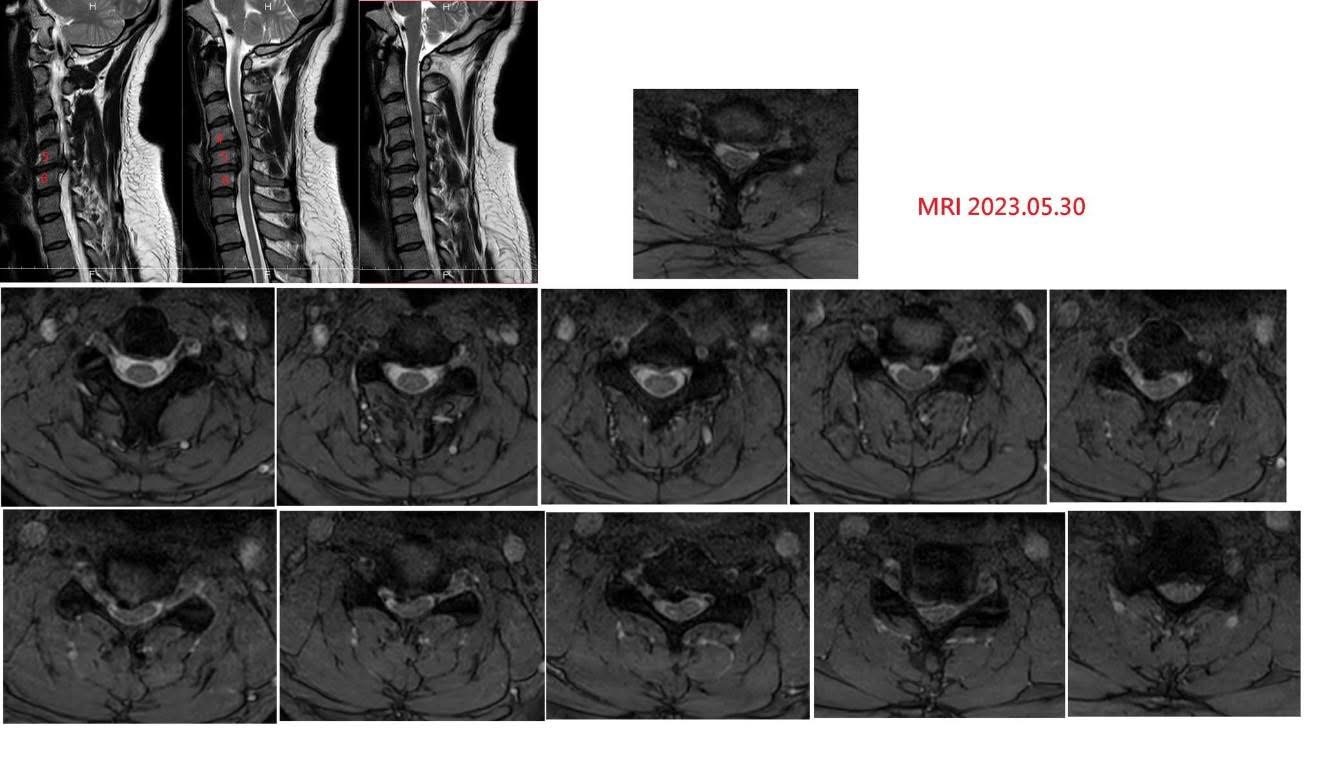

‼️這張MRI,他們說可能是危機!我卻看見生機

他帶來的MRI確實可怕:C5/6椎間盤突出明顯壓迫脊髓,蜘蛛網膜下腔幾乎不見。

但我們看得更細。

沒有明顯T2高信號(代表脊髓尚未變性)、沒有空洞症(那條白線是中央管延續)、沒有OPLL骨化(後縱韌帶乾淨),而且患者也做了斷層掃描排除那塊壓迫是鈣化。

也就是說——這不是「硬壓迫」,是「軟壓迫」;不是無法逆轉,而是尚可挽回的生機。

神經外科確實看到的是手術適應症;我們看到的是結構鬆解的可能性。